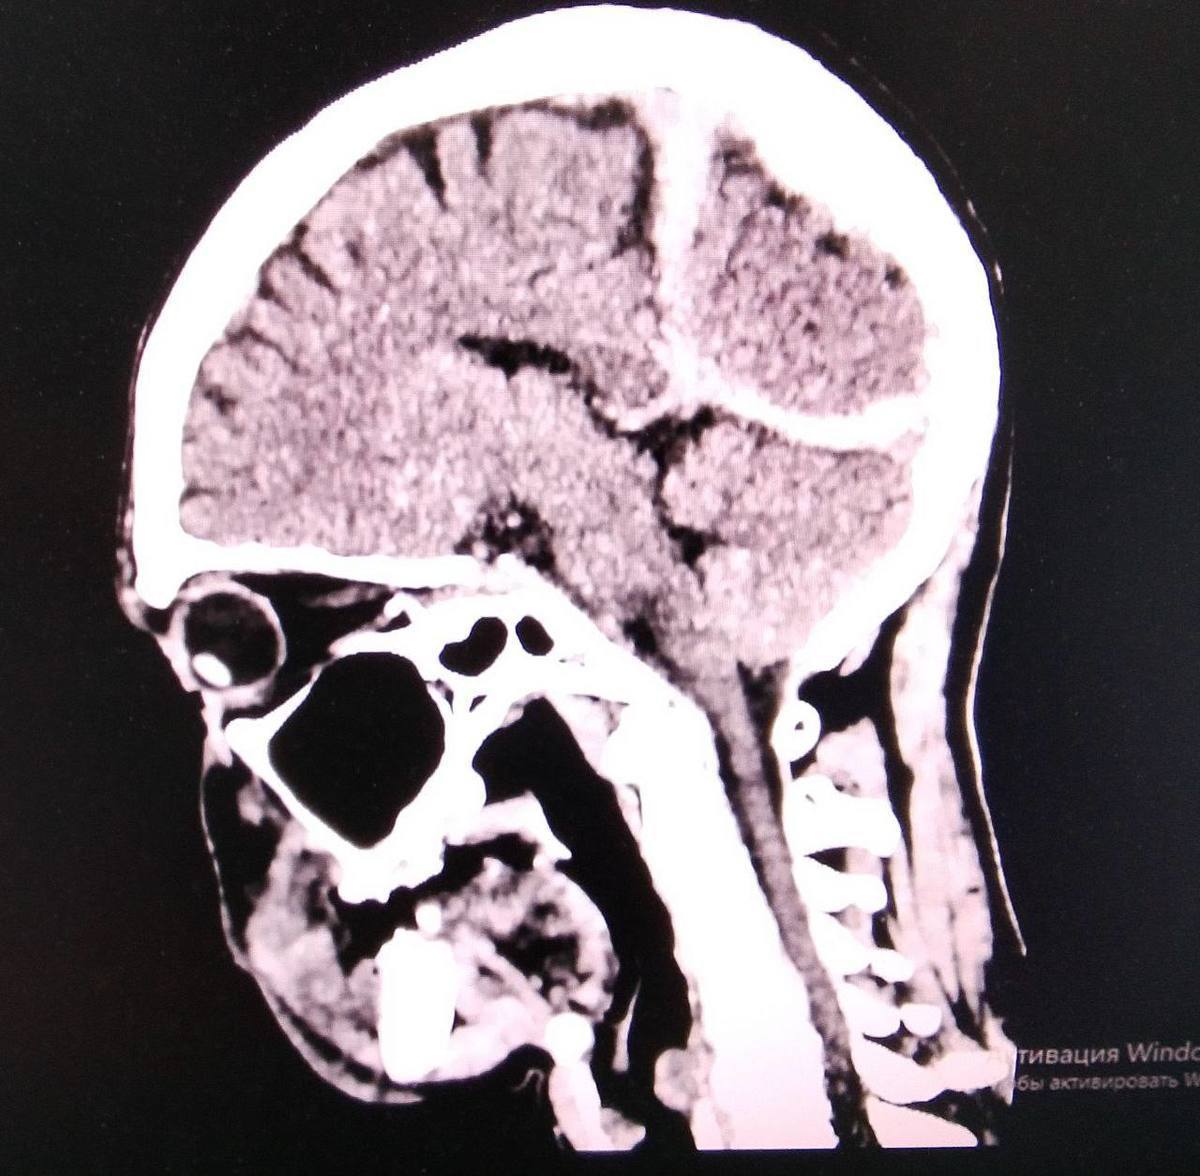

Пострадавшего случайно обнаружили местные жители и вызвали скорую помощь. Его экстренно доставили в Спасскую городскую больницу. Обследование показало субдуральную гематому, ушиб головного мозга, рану головы и выраженное переохлаждение, состояние оценивалась как тяжело. Благодаря оперативным действиям медиков мужчину удалось стабилизировать и привести в сознание. Сейчас он находится под наблюдением и проходит необходимое лечение, сообщает ТГ канал "Спасск-Дальний. Нововсти".